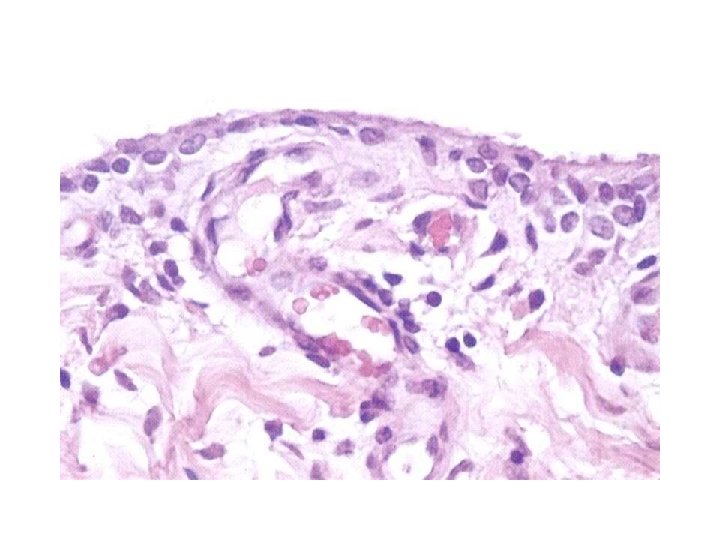

Synovial joints ØSynovium produce synovial fluid and composed of 1 -4 layers of cells ØCells vary from flat to cuboidal or polyhedral in shape ØTwo cell types defined: -Type A are phagocytic and have numerous lysosomes - Type B have abundant RER and produce protein ØThese layers of cells supported by a loose fibrocollagenous tissue containing adipocytes, mast cells, fibroblasts and macrophages

Synovial joints öThe synovial membrae has an abundant blood , lymph, and nerve supply running in the loose fibrocollagenous tissue öSynovial fluid contains of hyaluronic acid and glycoprotein(Lubricin) combined with a filtrate of plasma öThe synovial membrane supported by dense fibrocollagenous tissue ( Fibrous layer) öThe joint supported by some internal and external ligaments